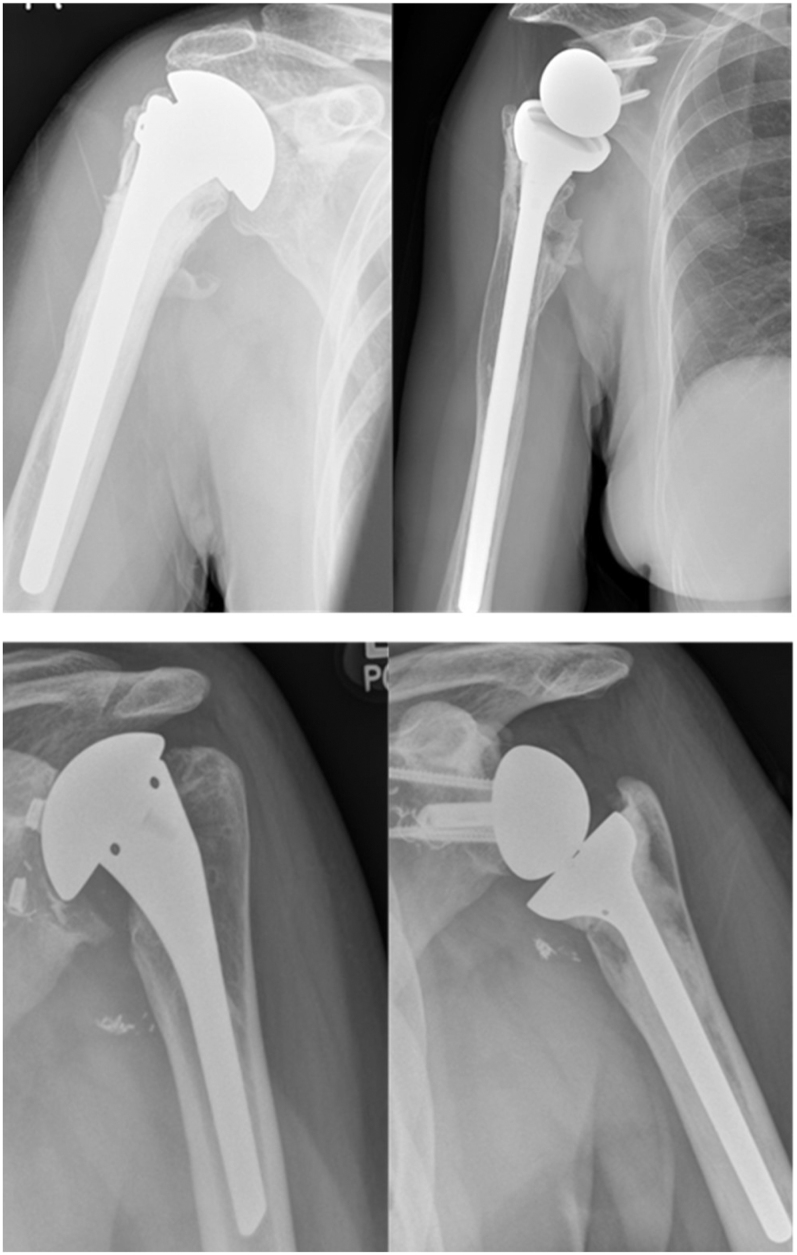

由于创伤性损伤、炎症性关节炎、缺血性坏死、退行性关节疾病的发生率上升以及高要求运动和职业活动的增加,55岁以下患者越来越多地使用肩关节置换术。解剖性肩关节置换术(ASA)仍然是年轻患者的首选手术选择,这些患者的肩袖完整,肩胛盂畸形最小,保留了自然的生物力学,力量和活动范围,并且显示出10-15年的高长期植入存活率。尽管预后良好,但ASA存在潜在的长期风险,包括植入物磨损、假体松动、关节盂糜烂和进行性肩袖退变,尤其是对体力活动的年轻患者。反向肩关节置换术(RSA)在复杂的临床情况下提供了一个有价值的替代方案,其特征是不可修复的肩袖撕裂,广泛的盂骨丢失,严重的解剖破坏或先前的手术失败。对于原发性骨关节炎和完整的肩袖患者,RSA可作为ASR的替代方案,在60岁以上的患者中具有良好的临床效果和生存率。RSA也被成功地用于55岁以下的患者,并取得了良好的短期效果。RSA在年轻、活跃的个体中的寿命和可靠性仍然值得关注。ASA可以修改为RSA,临床效果良好,而RSA失败是极具挑战性的。如果我们接受ASA会随着时间的推移而失效,那么主ASA应该允许对RSA进行轻松修订。模块化假肢设计的最新进展促进了从ASA到RSA的更简单的修订。

Shoulder arthroplasty is increasingly utilised among patients under 55 years of age due to rising incidences of traumatic injuries, inflammatory arthritis, avascular necrosis, degenerative joint diseases and heightened participation in demanding sports and occupational activities. Anatomic shoulder arthroplasty (ASA) remains the preferred surgical option for younger patients with intact rotator cuffs and minimal glenoid deformities, preserving natural biomechanics, strength and range of motion, and demonstrating high long-term implant survival rates at 10-15 years. Despite favourable outcomes, ASA carries potential long-term risks including implant wear, prosthetic loosening, glenoid erosion and progressive rotator cuff degeneration, particularly relevant for physically active younger patients. Reverse shoulder arthroplasty (RSA) offers a valuable alternative in complex clinical scenarios characterised by irreparable rotator cuff tears, extensive glenoid bone loss, severe anatomical disruption or previous surgical failures. RSA can be used as an alternative to ASR for primary osteoarthritis and an intact rotator cuff, with excellent clinical outcomes and survivorship in patients over 60. RSA is also being used successfully in patients under the age of 55 with excellent short-term results. There remain concerns regarding the longevity and reliability of RSA in younger, highly active individuals. ASA can be revised to RSA with good clinical outcomes, while failure of RSA is extremely challenging to address. If we accept that ASA will fail with time, then the primary ASA should allow for ease of revision to an RSA. Recent advances in modular prosthetic designs facilitate simpler revisions from ASA to RSA.